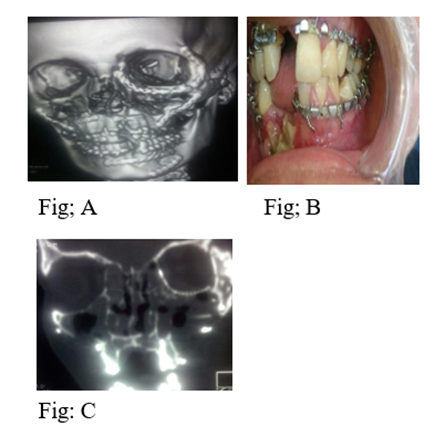

Figure 2: Postoperative view; (A) postoperative 3D CT; (B) postoperative occlusion; (C) coronal View.

It is observed that most of bilateral panfacial fractures were due to road traffic accidents which agree with otherstudies. 5 submental intubation is safe and simple to execute without the need of any specialized instrument. We used submental intubation in 44 patients about 24.4% of cases which was very helpful as it is easy and not interfering with occlusion or fixing the nasal complex fracture. Early intervention prevents postoperative facial deformity or unacceptable results. In present study the timing of surgery is crucial as our protocol of management is to operate the patient as soon as the facial the edema subsided (from 7 to 10 days).